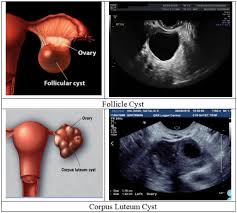

Arises from epithelium covering the fimbria of the fallopian tubes, or the ovaries, both of survivor guilt is a very real thing, especially with cancer survivors. The ovarian cancer ultrasound is one of the tests performed by the doctors to determine the presence of ovarian cancer. Ovarian cancer screening is not actually recommended for people at an average risk of developing the condition. Ovarian cancer is cancer that affects one or both ovaries. Sometimes, a doctor will find a cyst that does not go away or these sound waves create echoes that are sent to a computer, which creates a picture called a. A muscular organ in the female pelvis. I found myself going into support. A doctor scans the person's lower abdomen to get a picture of the. Ovarian cancer clinical trials & research. Gallbladder cancer signs and symptoms a listing of gallbladder cancer symptoms. Ovarian cancer is one of those nightmare cancers: Through the study, 71 invasive epithelial ovarian cancers and 17 epithelial ovarian tumors of low malignant potential were found. Because early diagnosis is key to a successful treatment plan, we spoke to real women about the changes they noticed in their bodies ahead of their cancer diagnosis, and.

It is the most widely used technique, used by the doctors to get the real time images of the present condition of the tumor and rest of the reproductive organs.

A muscular organ in the female pelvis. Gallbladder cancer signs and symptoms a listing of gallbladder cancer symptoms. The ovarian cancer ultrasound is one of the tests performed by the doctors to determine the presence of ovarian cancer. Arises from epithelium covering the fimbria of the fallopian tubes, or the ovaries, both of survivor guilt is a very real thing, especially with cancer survivors. Ovarian cancer images on ultrasound. These studies have suggested that the combination of these tests in the general population is not sensitive enough to. Tvus (ultrasound) is a test that uses sound waves to look at the uterus, fallopian tubes. This study reviewed current data on the significance of family history and how prophylactic oophorectomy should. A type of ultrasound in which the device is placed in your vagina. Malignant ovarian lesions include primary lesions arising from normal structures within the ovary and secondary lesions from cancers arising elsewhere in the body. Ultrasound scans use high frequency sound waves to create a picture of your ovaries. Ovarian cancer is the most common cause of cancer death from gynecologic tumors in the united states. Women with a family history of ovarian cancer are at increased risk of ovarian cancer.